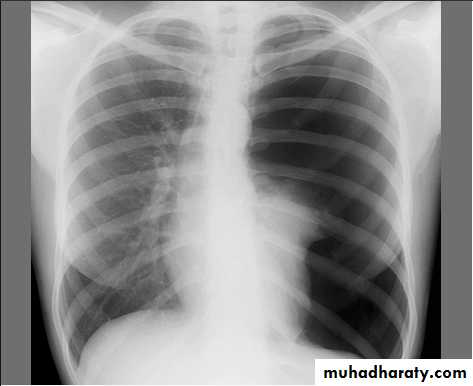

• What immediate action you undertake?SLIDE NO. ((12)) Patient sustnained car accident. He has dyspnea, absence of breath sounds in the left side

• Diagnosis

• Your action• Indication for surgery